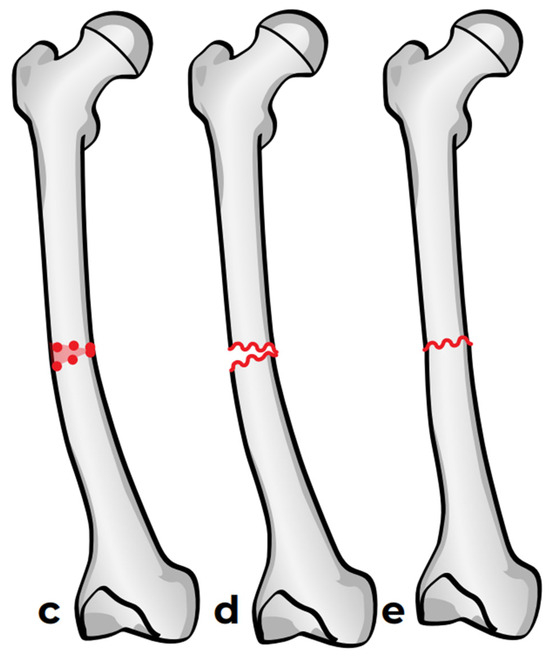

Two options are available: the first one is a straight-cut osteotomy using an oscillating saw, which creates a smooth planar surface on either side (Figure 6a). This method, however, provides minimal rotational stability once the bone segments are reduced (Figure 6b). Furthermore, the thermal injury generated by the power saw may have a negative effect on bone healing at the osteotomy site. To address these limitations, we used a multiple drill hole osteotomy technique, in which closely spaced drill holes are made along the planned osteotomy plane before making the cut (Figure 6c). This results in opposing surfaces being rugged and not smooth (Figure 6d). This interdigitation acts as a mechanical interlock between the bone fragments once reduced, which offers some rotational stability and reduces the need for fixation hardware (Figure 6e).

Figure 6.

Osteotomy techniques. (a,b): Osteotomy using an oscillating saw. (c–e): Osteotomy using multiple drill holes and an osteotome.